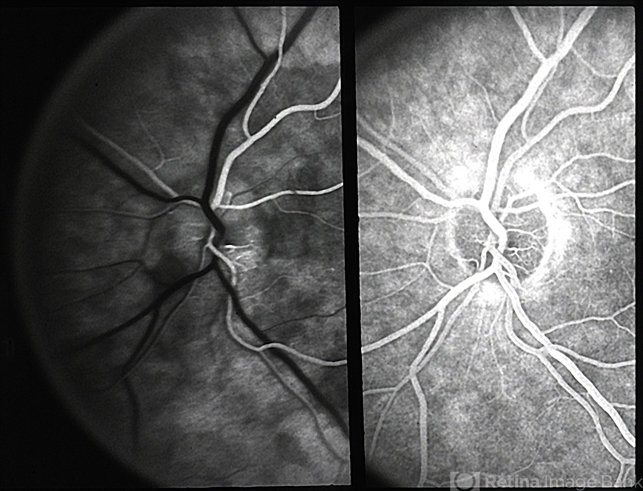

- anterior ischemic optic neuropathy

- Fluorescein for anterior ischemic optic neruopathy.